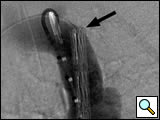

Figure 1: Left anterior oblique aortogram obtained with measuring pigtail catheter demonstrating aortic arch anatomy and location of aortic transection.

The patients are usually intubated as part of their initial resuscitation and have general anesthesia provided by an anesthesiology team for the procedure. In our institution, the procedure is performed in a conventional angiographic suite using ceiling-mounted Siemens Axiom ARTIS equipment (Erlangen, Germany). Patients are positioned supine with both groins prepped and draped. A 5-F graduated measuring pigtail catheter (Angiodynamics, Queensbury, NY) is inserted percutaneously via the left common femoral artery and a left anterior oblique arch aortogram is obtained to confirm arch anatomy and the location of the injury (Figure 1). Additional views, including selective vertebral artery injections, are performed as necessary.